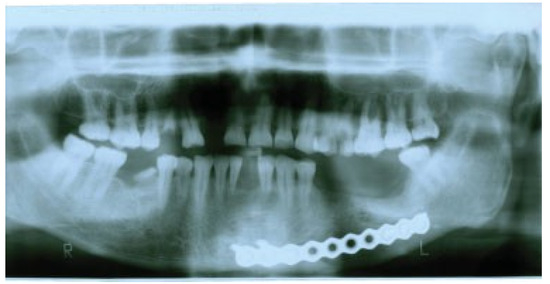

Pathologic Fractures in Bisphosphonate-Related Osteonecrosis of the Jaw—Review of the Literature and Review of Our Own Cases

Background Bisphosphonates are powerful drugs used for the management of osteoporosis and metastatic bone disease to avoid skeletal-related complications. Side effects are rare but potentially serious such as the bisphosphonate-related osteonecrosis...